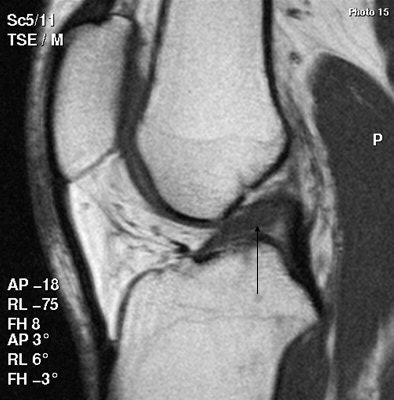

| Above, scan shows a tear extending into the undersurface of the posterior horn of the medial meniscus. Below, patient has a torn anterior cruciate ligament (ACL), shown as discontinuity toward the upper end of the ligament, along with swelling of the lower part. All images courtesy of Dr. Stephen Brearley. |